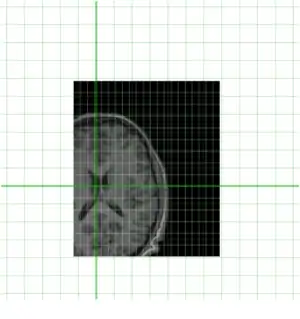

Clearly they are not aligned or "registered" to each other so we have to use a tool such as minctracc or mritoself in order to align them as such:

To do this we can use a command such as this:

minctracc -lsq9 indiv.mnc model.mnc align.xfm